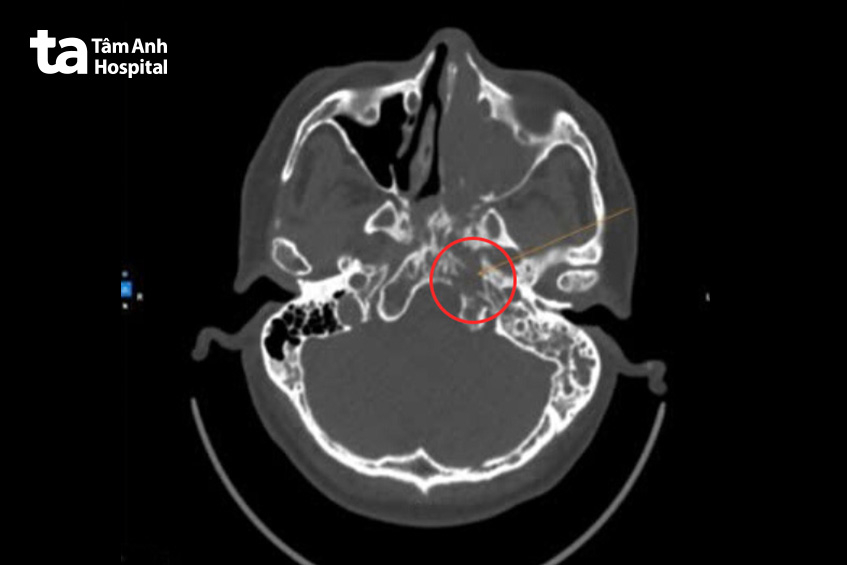

Kết quả chụp CT-scan ghi nhận tổn thương choán chỗ xoang hàm trái, lan vào hốc mũi qua lỗ thông xoang. Tổn thương lan vào lấp đầy xoang sàng, xoang trán và xoang bướm trái, phát triển về phía cửa mũi sau trái, lấp đầy vòm mũi họng hai bên. Tổn thương hủy xương clivus (xương nằm ở nền sọ) trái, tụ dịch khí chũm bào trái và quanh các xương con bên trái, theo dõi hạch góc hàm trái.

Bác sĩ Phát chẩn đoán người bệnh viêm mũi xoang xuất tiết, theo dõi u hốc mũi. Qua đánh giá trên lâm sàng và hình ảnh học, nghi ngờ khối u ác tính, chỉ định sinh thiết.